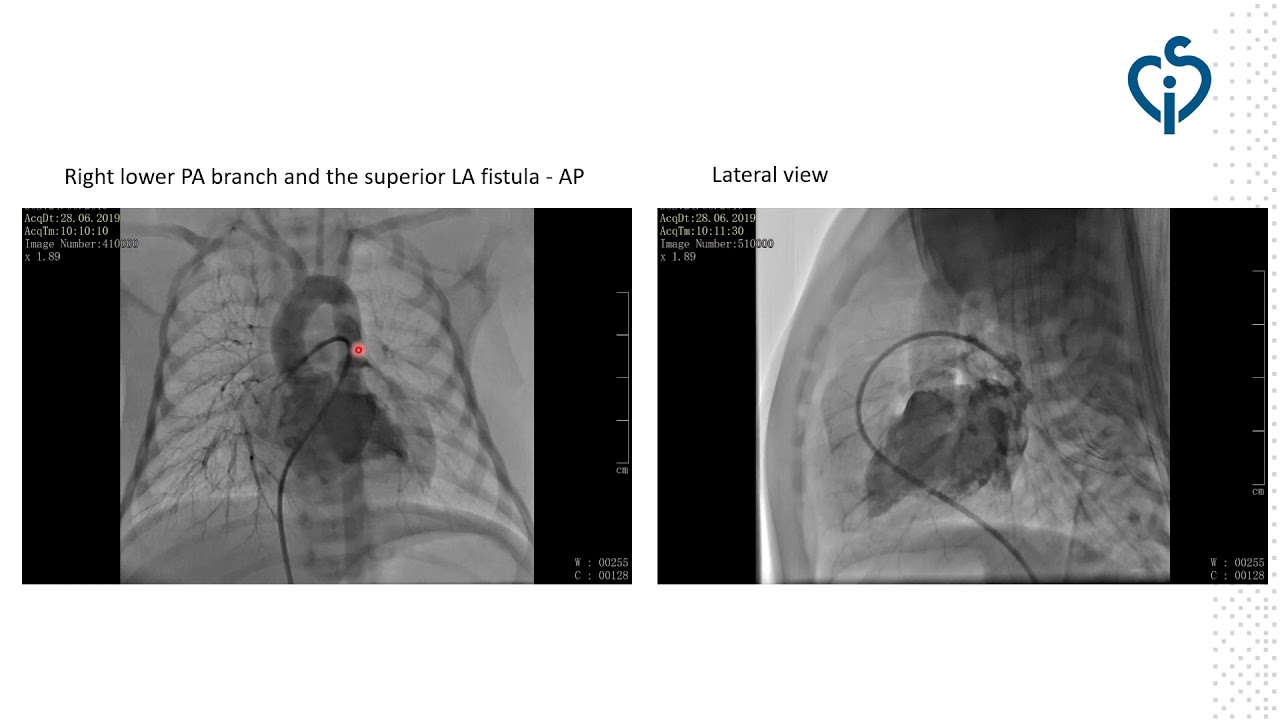

Successful transcatheter treatment of right pulmonary artery‑to‑left atrium (RPA-to-LA) fistula in a newborn with severe cyanosis

By: Elisaveta Levunlieva-Ivanova, National Heart Hospital, Sofia, Bulgaria

Transcatheter closure of right pulmonary artery to left atrium fistula under transesophageal echocardiography guidance (A case report)

By: Yasmin Abdel Razek, Ain Shams University, Cairo, Egypt